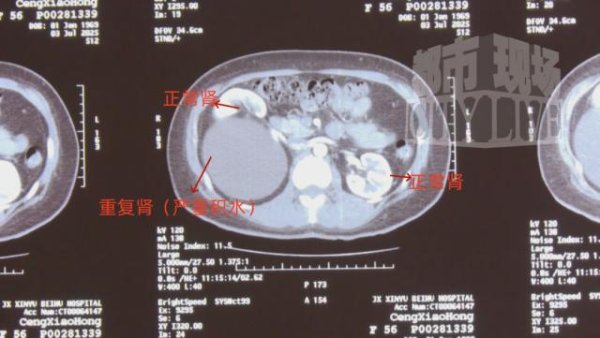

最近,江西新余的郑女士因长期腰痛难忍前往医院就诊胜宇配资,不料这检查结果让人大吃一惊,她的体内比咱们多了一个肾! CT 检查显示,郑女士的的体内竟然有"三个肾"....